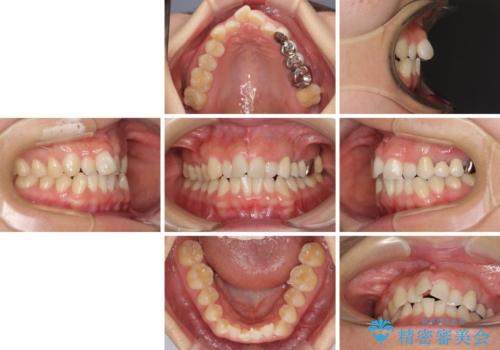

- 上下前歯のデコボコと銀歯のブリッジを気にして来院された患者様です。

装着されているブリッジを切断して矯正治療を行うことや、手間をかけずに早めに治療を終えたいとのことで、目立たないワイヤー装置による矯正治療を行うこととしました。

矯正治療後には切断したブリッジをオールセラミックブリッジに置き換えることとしました。

捻れた前歯と銀歯のブリッジを治したい ワイヤー矯正とオールセラミックブリッジ